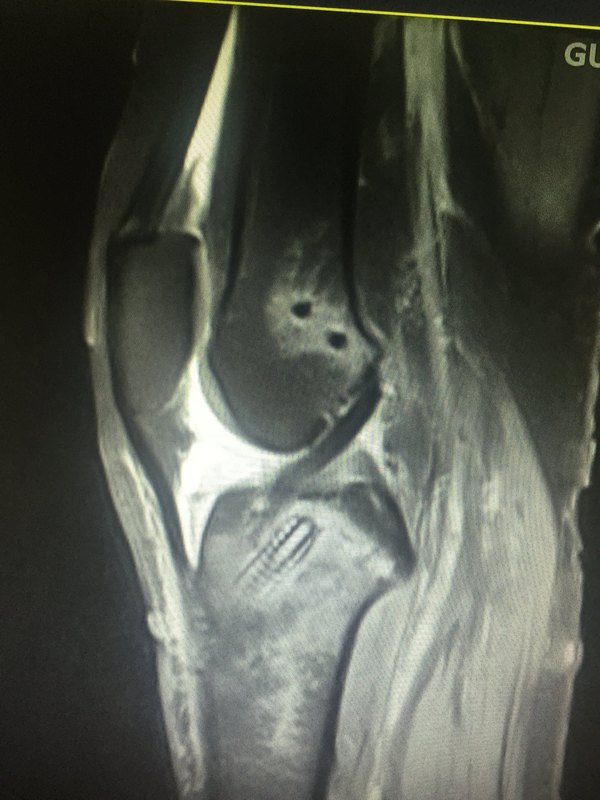

在美國約有900萬有癥狀,且經(jīng)影像學(xué)證實(shí)的膝關(guān)節(jié)骨關(guān)節(jié)炎患者。50歲以上的人群中患有半月板撕裂(退變撕裂)者高達(dá)35%,其中三分之二都沒有癥狀。半月板損傷(退變)在患有骨關(guān)節(jié)炎的患者中患病率尤其高,臨床通常都進(jìn)行關(guān)節(jié)鏡下的半月板部分切除。該手術(shù)方式主要通過修正撕裂的半月板,使其邊緣變得穩(wěn)定、平整。同時(shí)清理部分炎性滑膜。美國,每年約有46.5萬例患者接受這一手術(shù)。 由于半月板撕裂(退變撕裂)合并膝關(guān)節(jié)骨關(guān)節(jié)炎的患病率很高,并且二者都有可能沒有任何癥狀,這對(duì)于臨床決策來說是一個(gè)挑戰(zhàn):有癥狀的患者,其癥狀是來自半月板撕裂,還是骨關(guān)節(jié)炎,或者二者兼有。如果醫(yī)生懷疑癥狀來自半月板撕裂,通常會(huì)建議患者進(jìn)行關(guān)節(jié)鏡手術(shù)。但是經(jīng)臨床實(shí)驗(yàn)表明,關(guān)節(jié)鏡清理和非手術(shù),二者的結(jié)論都顯示,在24個(gè)月內(nèi)的功能改善和疼痛緩解方面,關(guān)節(jié)鏡清理沖洗和非手術(shù)相比,無論統(tǒng)計(jì)學(xué)還是臨床方面,都沒有明顯差異。臨床上通過理療卻能較好地改善功能、緩解疼痛。 但絕非半月板撕裂合并膝關(guān)節(jié)骨關(guān)節(jié)炎的老年患者都無關(guān)節(jié)鏡手術(shù)的指征,一旦發(fā)生因半月板撕裂而造成的膝關(guān)節(jié)絞索,還是應(yīng)該及時(shí)進(jìn)行關(guān)節(jié)鏡手術(shù)治療。